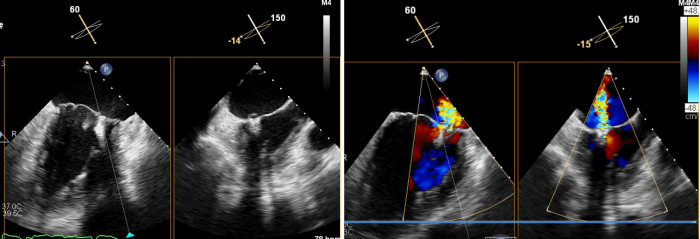

术后心脏彩超所示:二尖瓣无返流

术后,患者二尖瓣返流情况得到了明显改善,其他各项生理指标也均正常,术后第二天即可下床活动,呼吸困难和乏力症状显著缓解,心脏负荷明显减轻。术后心脏彩超结果显示,其左室射血分数上升到62%,生活质量获得极大提升。